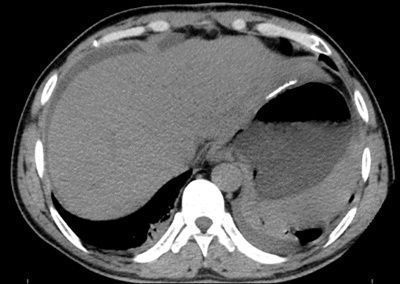

外伤性十二指肠破裂